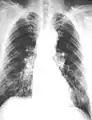

The abnormal chest x-ray and its interpretation remain the most important factors in establishing the presence of pulmonary fibrosis.[11] The findings usually appear as small, irregular parenchymal opacities, primarily in the lung bases. Using the ILO Classification system, "s", "t", and/or "u" opacities predominate. CT or high-resolution CT (HRCT) are more sensitive than plain radiography at detecting pulmonary fibrosis (as well as any underlying pleural changes). More than 50% of people affected with asbestosis develop plaques in the parietal pleura, the space between the chest wall and lungs. Once apparent, the radiographic findings in asbestosis may slowly progress or remain static, even in the absence of further asbestos exposure.[24] Rapid progression suggests an alternative diagnosis.

Extensive fibrosis of pleura and lung parenchyma.

Severe pleural fibrosis with focal calcification.

61 yr old working industrially with asbestos for decades.